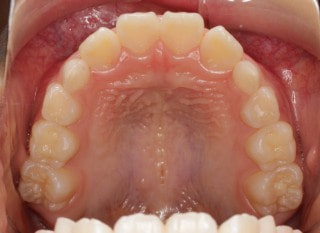

小児期第一段階

終了時